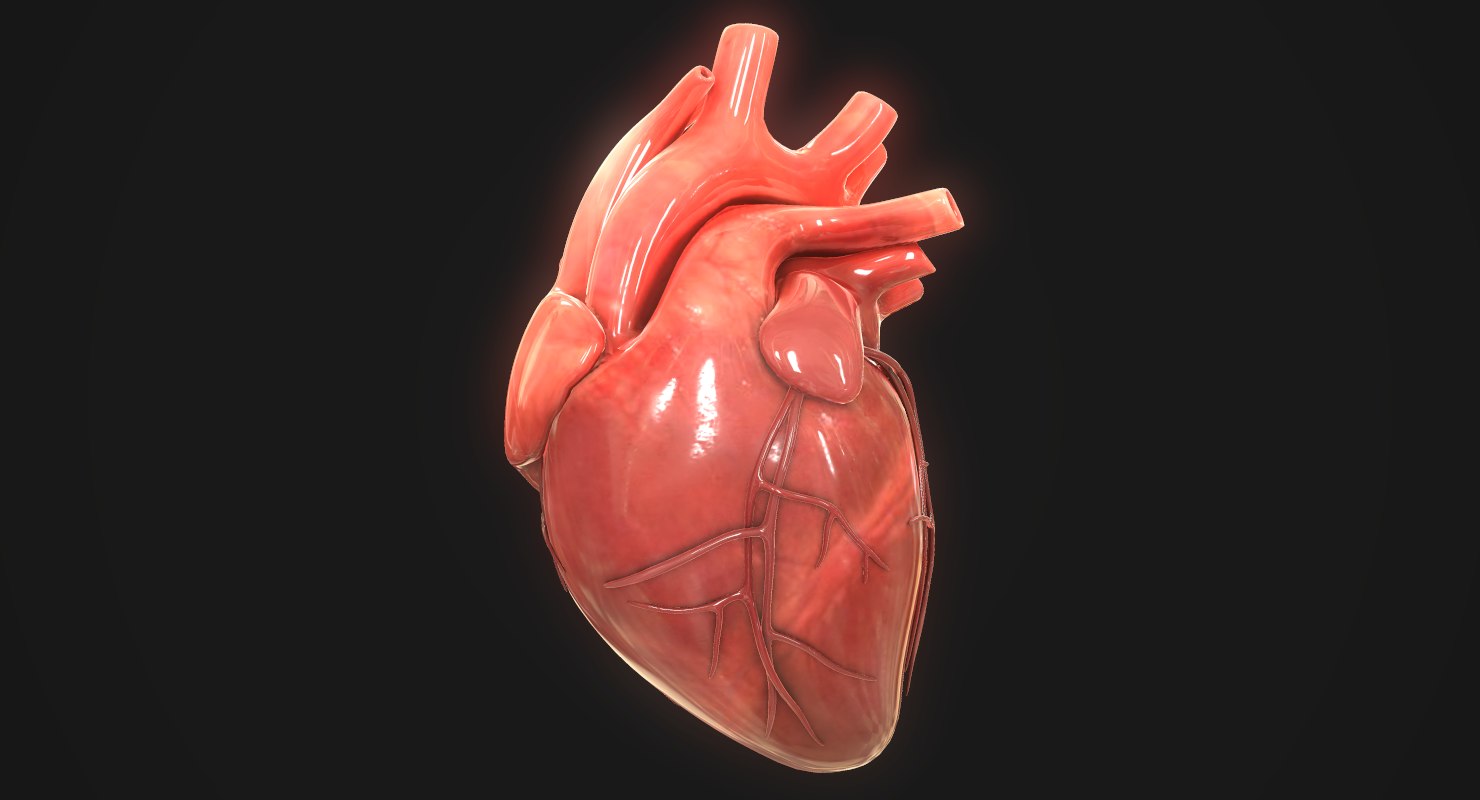

3d human heart  Animated Realistic Human Heart - Medically 3D asset

Heart by Rustamova on @DeviantArt | Anatomical heart art, Anatomy art, Heart drawing  3d human heart

3d human heart  Human Heart Pencil Drawing at GetDrawings | Free download

Human Heart Pencil Drawing at GetDrawings | Free download  3d human heart

3d human heart  3d human heart

3d human heart  3d human heart anatomy model